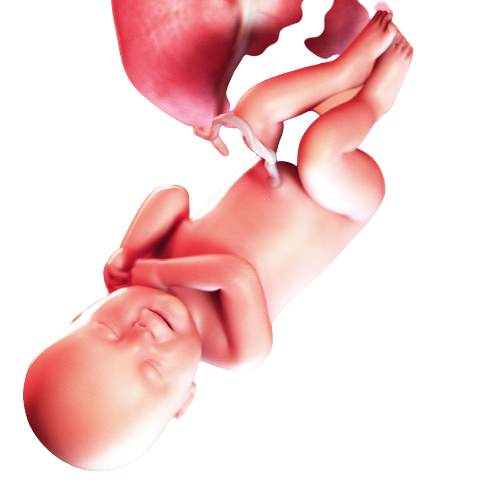

بەشی دووگیانی

بوونی بهرنامهی پری له نێو ئامێرهکهت گرنگه بۆ تهندروستی خۆت و کۆرپهکهت یاخود وهرگرتنی ئهزموون و زانیاری له خانمانی ترهوه